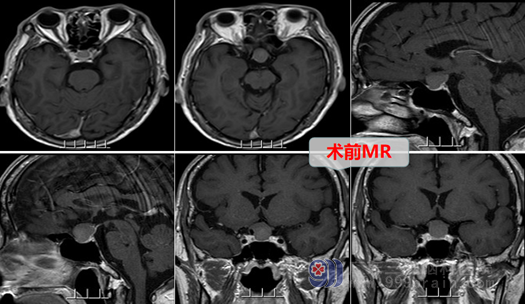

68岁汤叔2个月前无明显诱因出现头痛,呈阵发性,以左侧颞部胀痛为主,疼痛后又可自行缓解,在发作期间还出现2次短暂右侧肢体乏力,数分钟后自行缓解,但近来发展至疼痛难忍,便到当地医院就诊,行头颅MR示“左侧额叶放射冠急性脑梗塞,左侧大脑中动脉狭窄,鞍区占位等”,建议去专科医院治疗,汤叔经人介绍,找到了广东三九脑科医院欧阳辉教授,欧阳教授热情接待,并以“鞍区占位”收入神经外十科。

入院后神经外十科欧阳辉主任团队立即为他安排相关详细检查,MRI检查结果示:鞍区病变以Rathke’s囊肿可能性大。

外十科团队经过详细病情讨论,决定采用微创技术全麻下行内镜经鼻蝶鞍区rathke囊肿开窗引流术,术中磨除鞍底骨窗约1.5cm大小,钩刀“+字型”全层切开硬脑膜。见病变囊内容物灰白色,正常垂体组织位于下后方,鞍膈塌陷,流出全部囊液,切除部分囊壁,检查无脑脊液漏,无明显出血,顺利结束手术。术后复查头颅CT示鞍区病变切除满意,未见积血,加行了药物对脑梗塞的治疗。几天后,汤叔汤叔迅速好转,也未出现尿崩、头痛等症状。